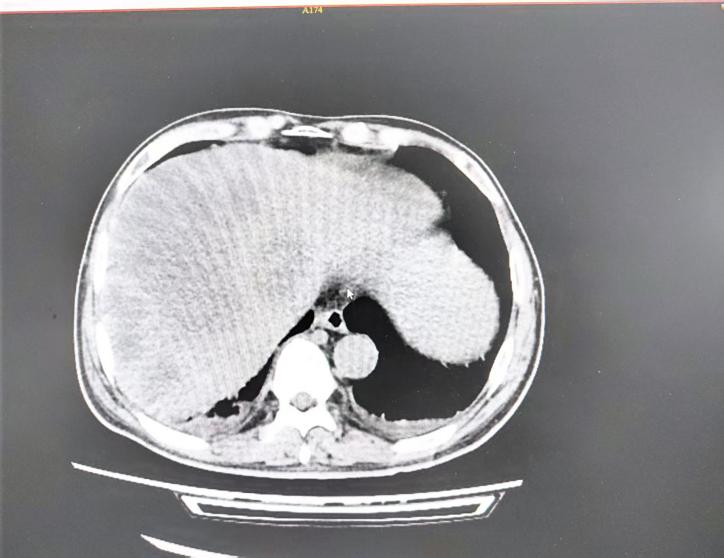

2025年08月31日CT示: